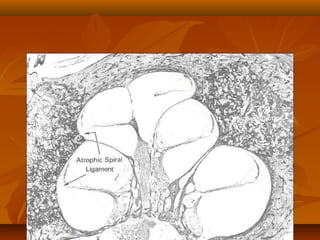

Hyalinization of the spiral ligament

Hyalinization of thespiral ligament